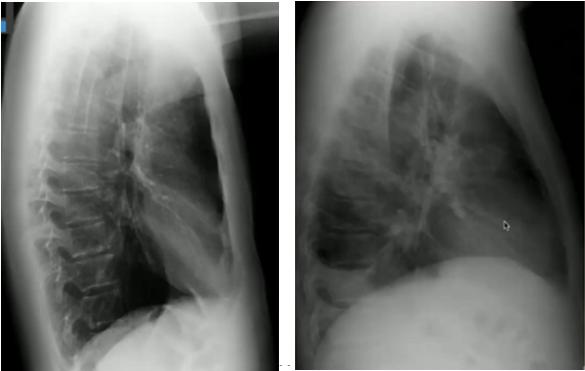

图14.“脊柱征”:位于心影后的下叶肺炎在正位片中不易看出,侧位片中可表现为椎体变白正常侧位片(左)与下叶肺炎(右)